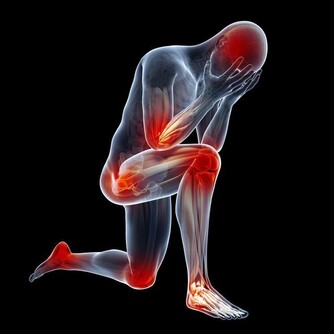

7、自測人體老化程度:金雞獨立

閉上雙眼,金雞獨立(單腿站立),測測能站多長時間。